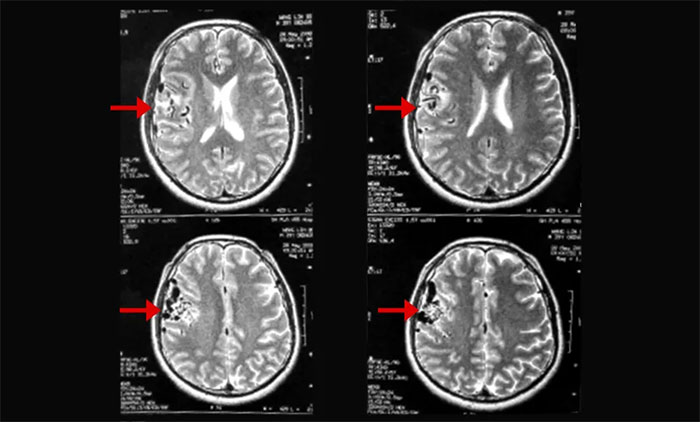

▲ 磁共振影像提示右顳頂動(dòng)靜脈畸形

上海藍(lán)十字腦科醫(yī)院腫瘤科(放療)頭部伽瑪?shù)督M主任陳琦曾收治一位青年男性AVM患者胡某(化名)。該患者曾因頭暈頭痛、口齒不清在當(dāng)?shù)蒯t(yī)院就醫(yī),影像檢查提示“右顳頂占位”,考慮為腦腫瘤可能性大,采取藥物對(duì)癥治療。其后,患者因前額頂部位脹痛找到陳琦主任團(tuán)隊(duì)尋求進(jìn)一步治療方案。通過(guò)影像學(xué)檢查,提示病灶區(qū)域潛在血管異常,診斷排除腦腫瘤,而是右顳頂動(dòng)靜脈畸形。